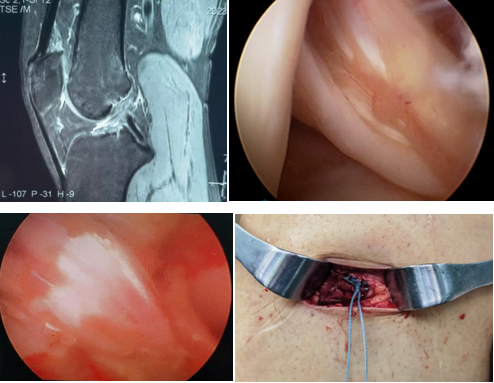

近日,一名31岁男性因打篮球扭伤致“右膝关节疼痛伴行走不稳半年”入院,术前诊断:前交叉韧带部分断裂。考虑患者年轻且有较高的运动恢复需求,在骨科病院刘时璋主任医师的指导下,由冯敏副主任医师主刀完成黑料网首例关节镜辅助下前交叉韧带损伤“保残+全内”重建术。患者第二日即下地活动,第三天顺利出院。

ACL的保残重建具有有效促进ACL移植物血管再生,促进损伤ACL本体感觉的恢复,以及防止ACL术后隧道扩大等多种技术优势。而ACL的全内重建技术是国际上新近发展出现的另一项新技术,相比传统方法,它仅需获取自身单根肌腱,而且所需长度远小于传统重建方法。另外,此技术保留了更多的骨皮质及骨膜,术后疼痛更少,腱骨愈合更佳,同时有效降低了术后感染风险,避免了传统方式界面螺钉对肌腱的切割作用。